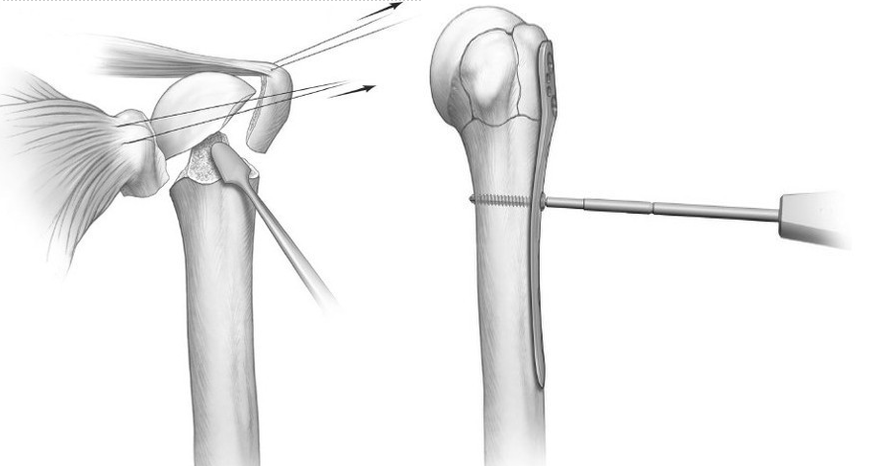

1、经皮穿针内固定适应证:此技术相对微创,发生骨坏死的机率相对较小,但稳定性不足,技术要求高。可用于不稳定的两部分外科颈骨折,也可用于更为复杂的三部分骨折或外展崁插的四部分骨折

一例外展崁插四部分骨折的前后位片:

器械辅助下复位骨折,经皮穿针内固定术的最终效果

该技术一般需要患者具有较好的骨密度,粉碎程度轻,结节完整,内侧壁支撑好,更为关键的是患者应具有较好的依从性。

预后:此技术一般可获得良好的愈合和功能恢复,如果术中无法获得良好的复位,应进行切开复位。